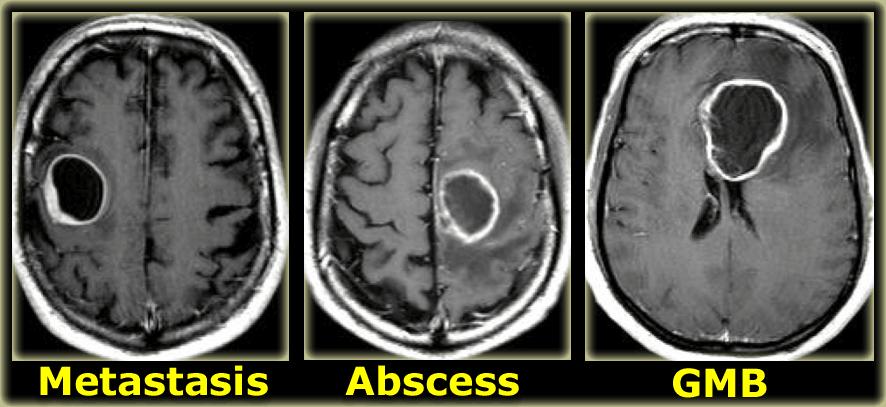

Ngấm thuốc dạng vòng

Ngấm thuốc dạng vòng được thấy trong di căn não và u thần kinh đệm độ cao.

Nó cũng được thấy trong các tổn thương không phải u như áp xe, một số mảng xơ cứng rải rác (MS) và đôi khi trong khối máu tụ cũ.

Bên trái là ba tổn thương ngấm thuốc dạng vòng khác nhau.